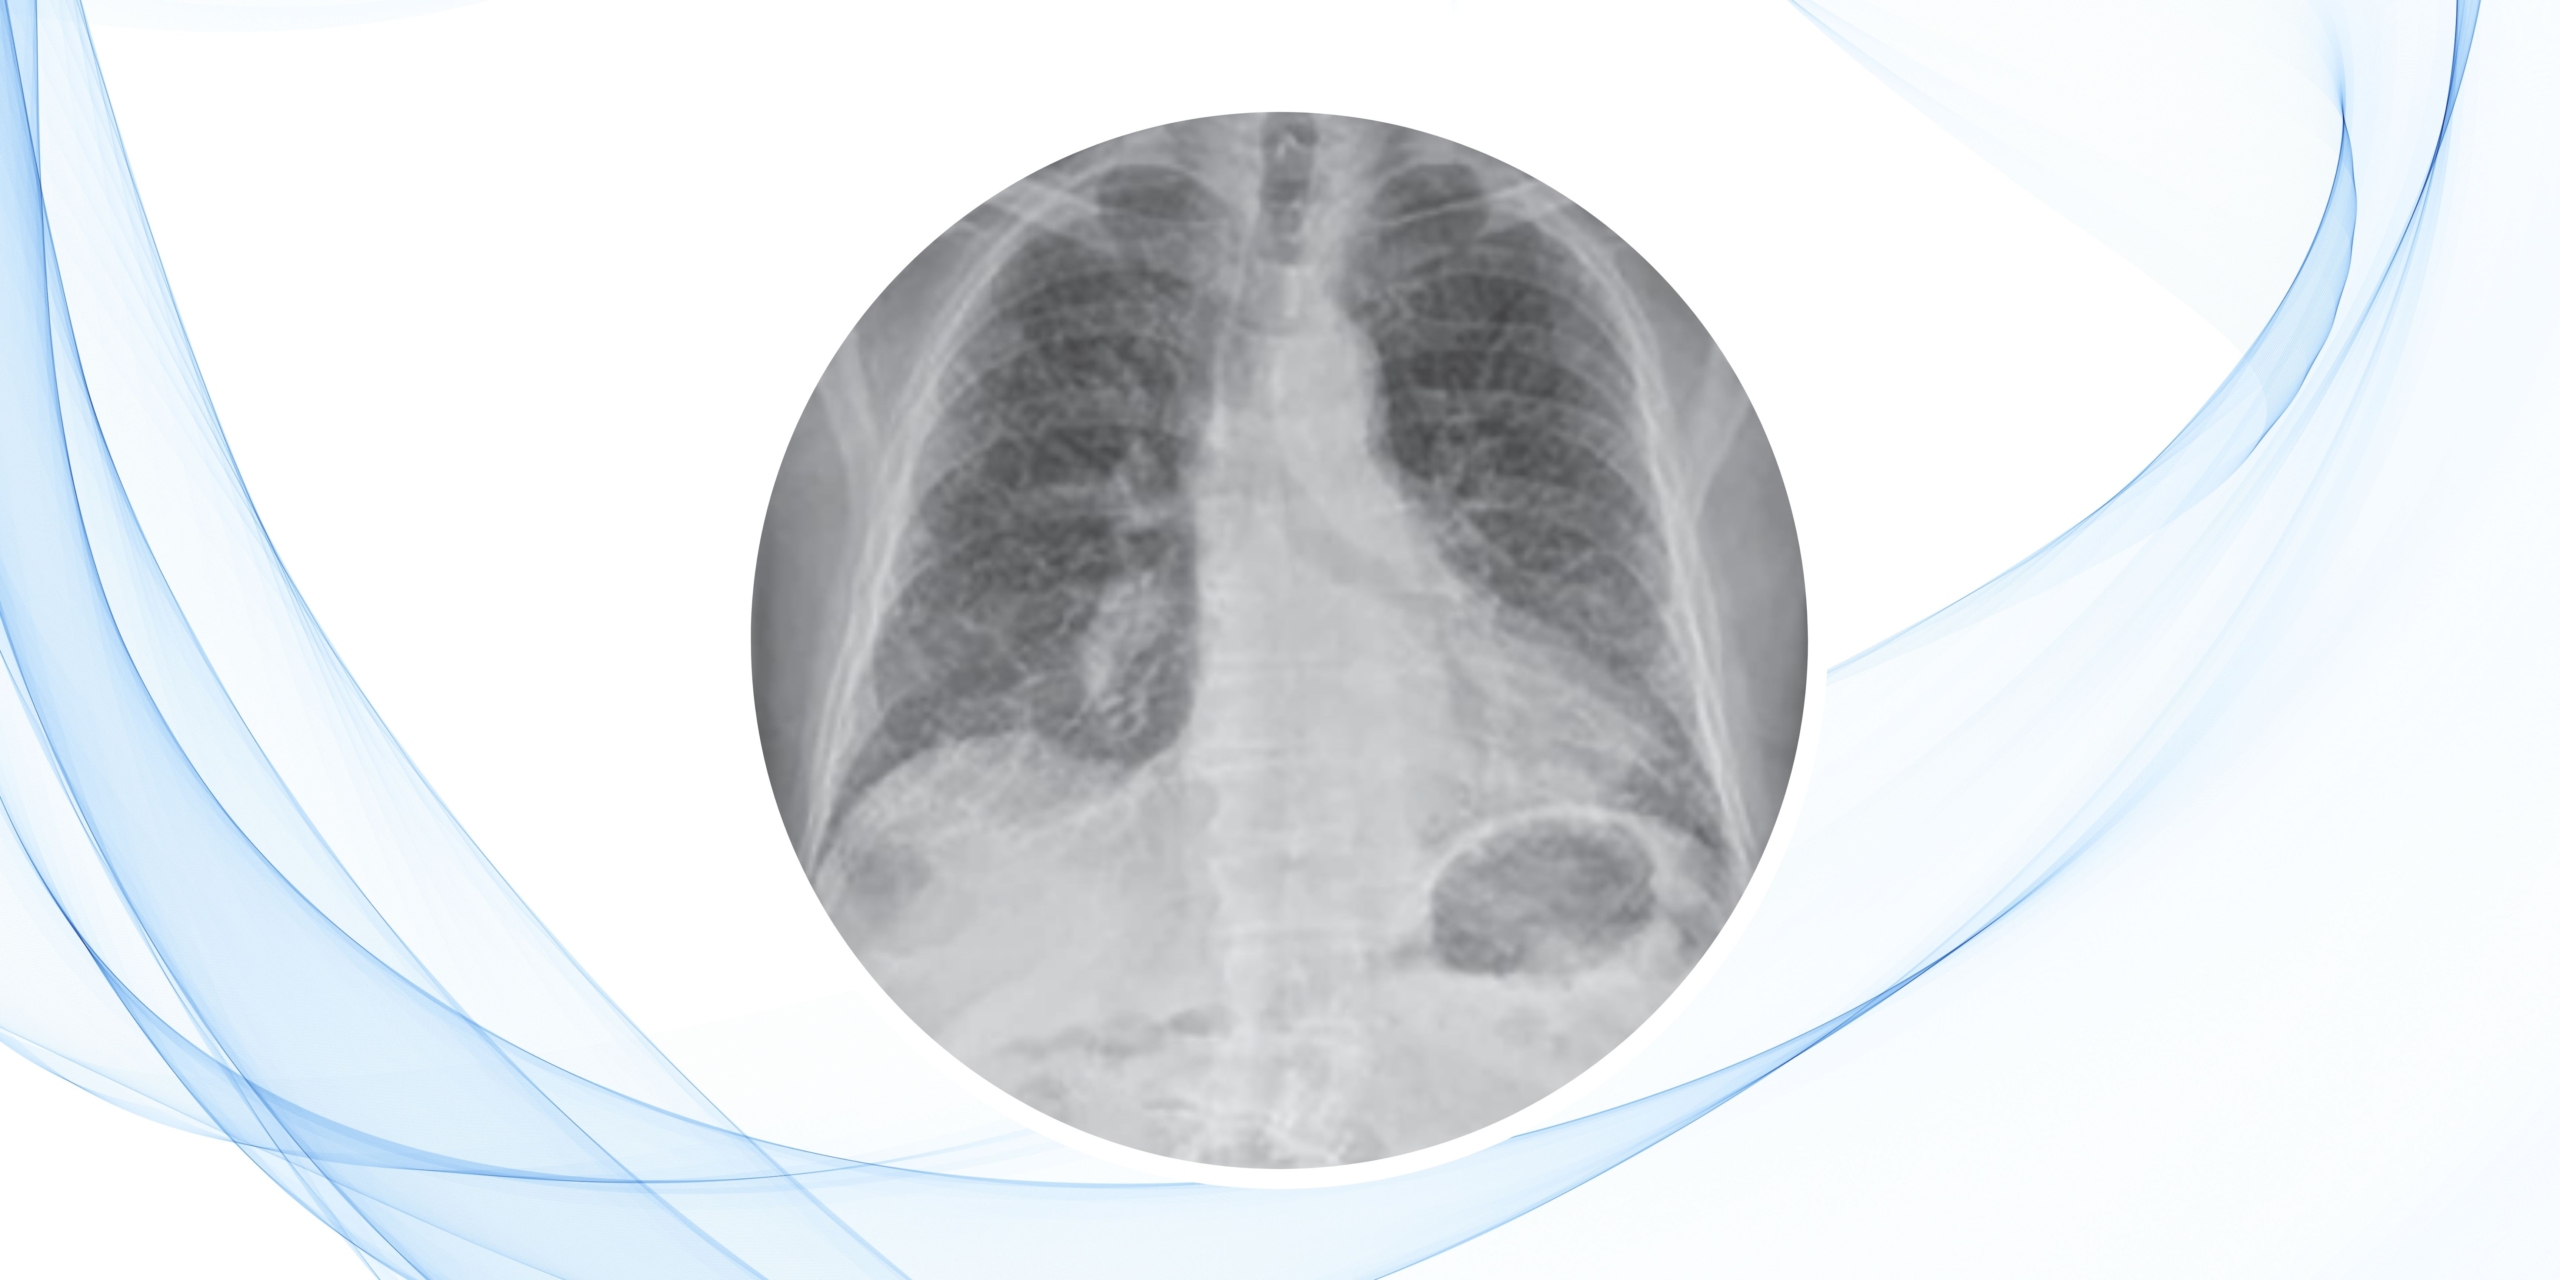

Un hombre de 65 años consultó por disnea progresiva de esfuerzo y tos seca de dos años de evolución. Había sido tratado inicialmente como EPOC con esteroides orales, broncodilatadores y antibióticos, sin mejoría. La radiografía de tórax mostró un patrón intersticial reticular basal, motivo por el cual fue remitido al neumólogo. El paciente era exfumador y oficinista jubilado, sin antecedentes de exposición nociva y con comorbilidades controladas (hipertensión y diabetes tipo 2). Su saturación de oxígeno era del 95% en reposo y no presentaba signos clínicos de enfermedad del tejido conectivo.